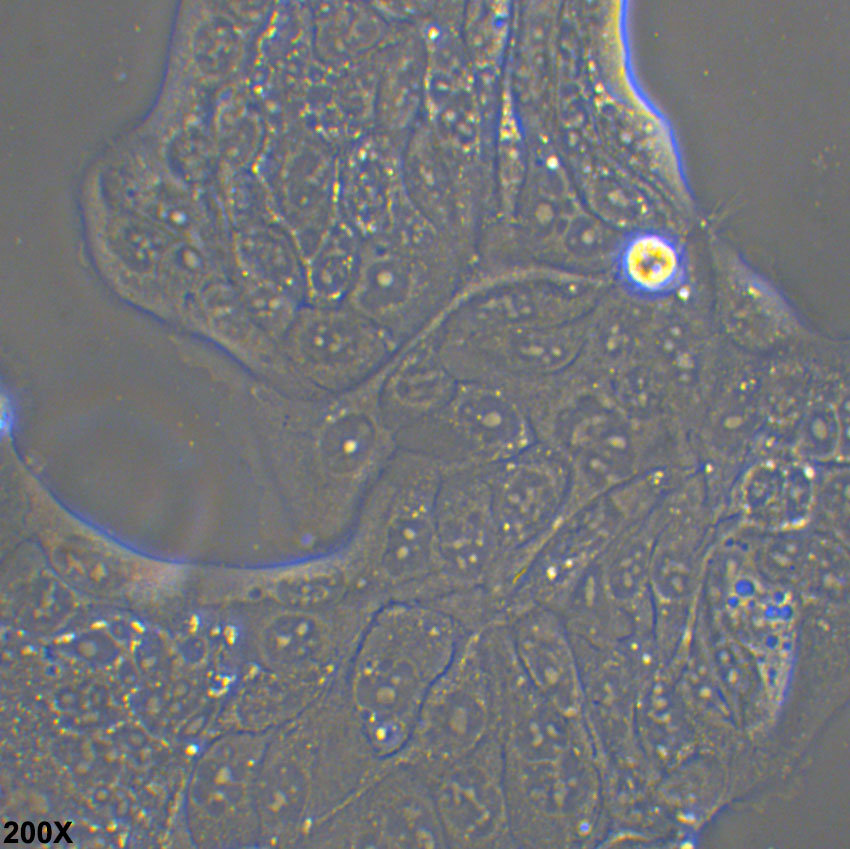

Calu-3人肺腺癌細胞(STR鑒定正確)

• 形態(tài)特征: 上皮細胞樣

• 生長特性: 貼壁

細胞成片生長,且生長速度較慢